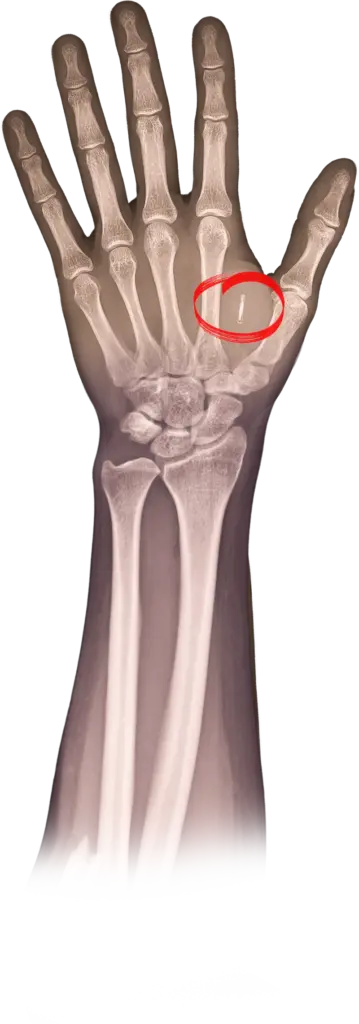

Wie voert de regie over deze zorgprocessen? Je hoeft geen futurist te zijn om te snappen dat goedwillenden en kwaadwillenden dit kunnen doen. Harari wees erop dat het menselijk lichaam gehackt kan worden. Futurist en innovatie-expert Peter Joosten onderkent dat. Joosten, die in 2015 een chip met zijn contactgegevens liet implanteren in zijn hand, wijst onder meer op commercieel gebruik door monitoring van hormonen, gedrag en DNA. Klantprofielen kunnen verfijnd worden door klikgedrag te combineren met de cortisol- en dopaminespiegel. Daaruit kan bijvoorbeeld worden opgemaakt of iemand gevoelig is voor een aankoop of online gokverslaving. Als die data niet goed beschermd is, dan is dat een risico, stelt Joosten terecht.

Joosten adviseert zorginstellingen de ontwikkelingen rond IoB-technologie te blijven volgen en te kijken wat ermee kan. ‘Denk niet in losse devices maar in ecosystemen van netwerken, applicaties en cloud-infrastructuur.’ Hoewel hij zelf inmiddels twee chips in zijn hand heeft (‘ook een voor betalen’) is hij niet blind voor de risico’s van IoB. ‘Als de technologie vervangen moet worden, moet die uit het lijf en dat is niet zo makkelijk. Hoe zit het verder met het eigendomsrecht? Ik sprak eens een patiënt die een netvliesimplantaat had laten plaatsen om beter te kunnen zien. Prachtig, maar het bedrijf dat de technologie leverde ging failliet. Daar zit je dan met je implantaat. Verder adviseer ik zorginstellingen security by design vanaf de start mee te nemen, voor betere interoperabiliteit. IoB-devices moeten via een api kunnen praten met interne protocollen en het epd, anders heb je er nog niks aan.’